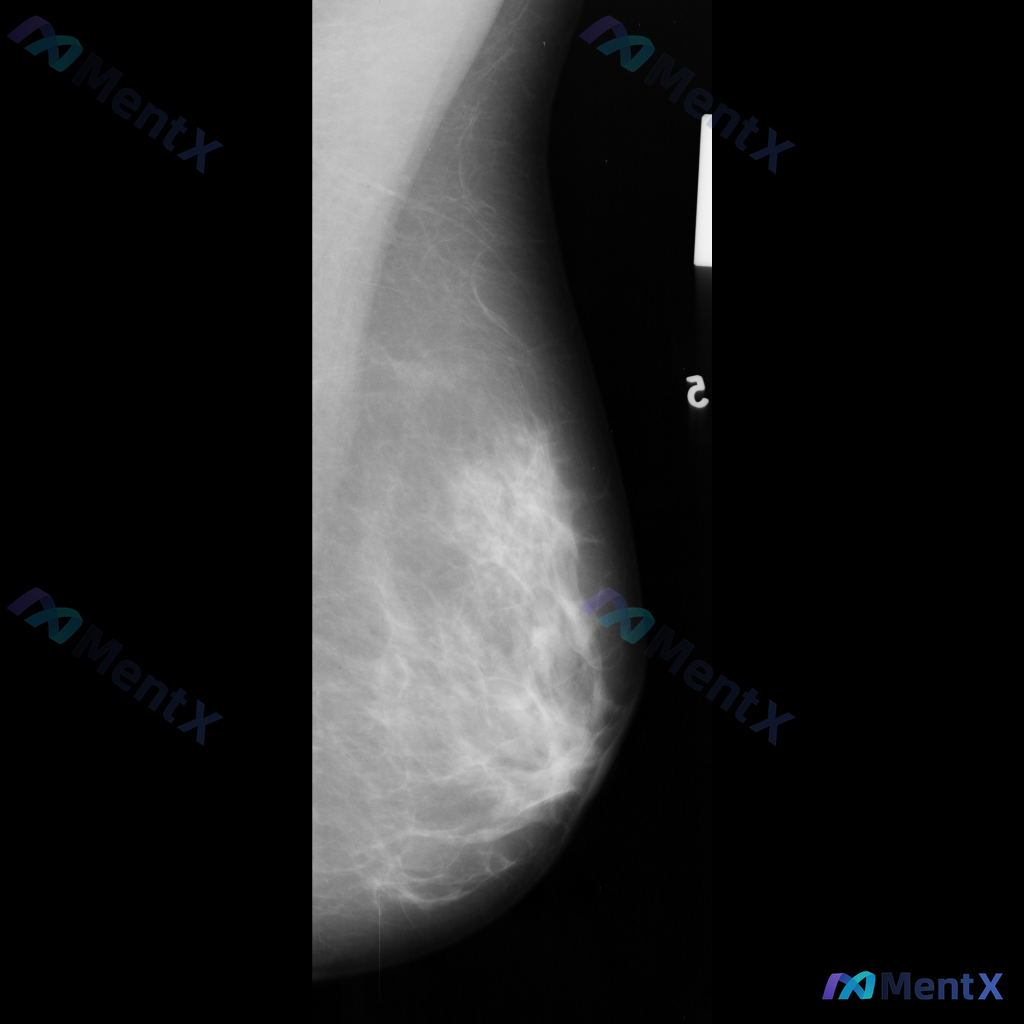

整理到一份乳腺钼靶的影像资料,和大家讨论一下: 目前只有左乳的内外斜位(MLO)视图,提示: - 左乳外侧象限可见一个局限性高密度肿块影 - 肿块形态呈卵圆形,边缘清晰 - 密度高于周围乳腺实质,与周围组织界限明确 - 未见明显结构扭曲、皮肤牵拉或典型恶性钙化等征象 - 乳腺类型为不均匀致密型(BI...